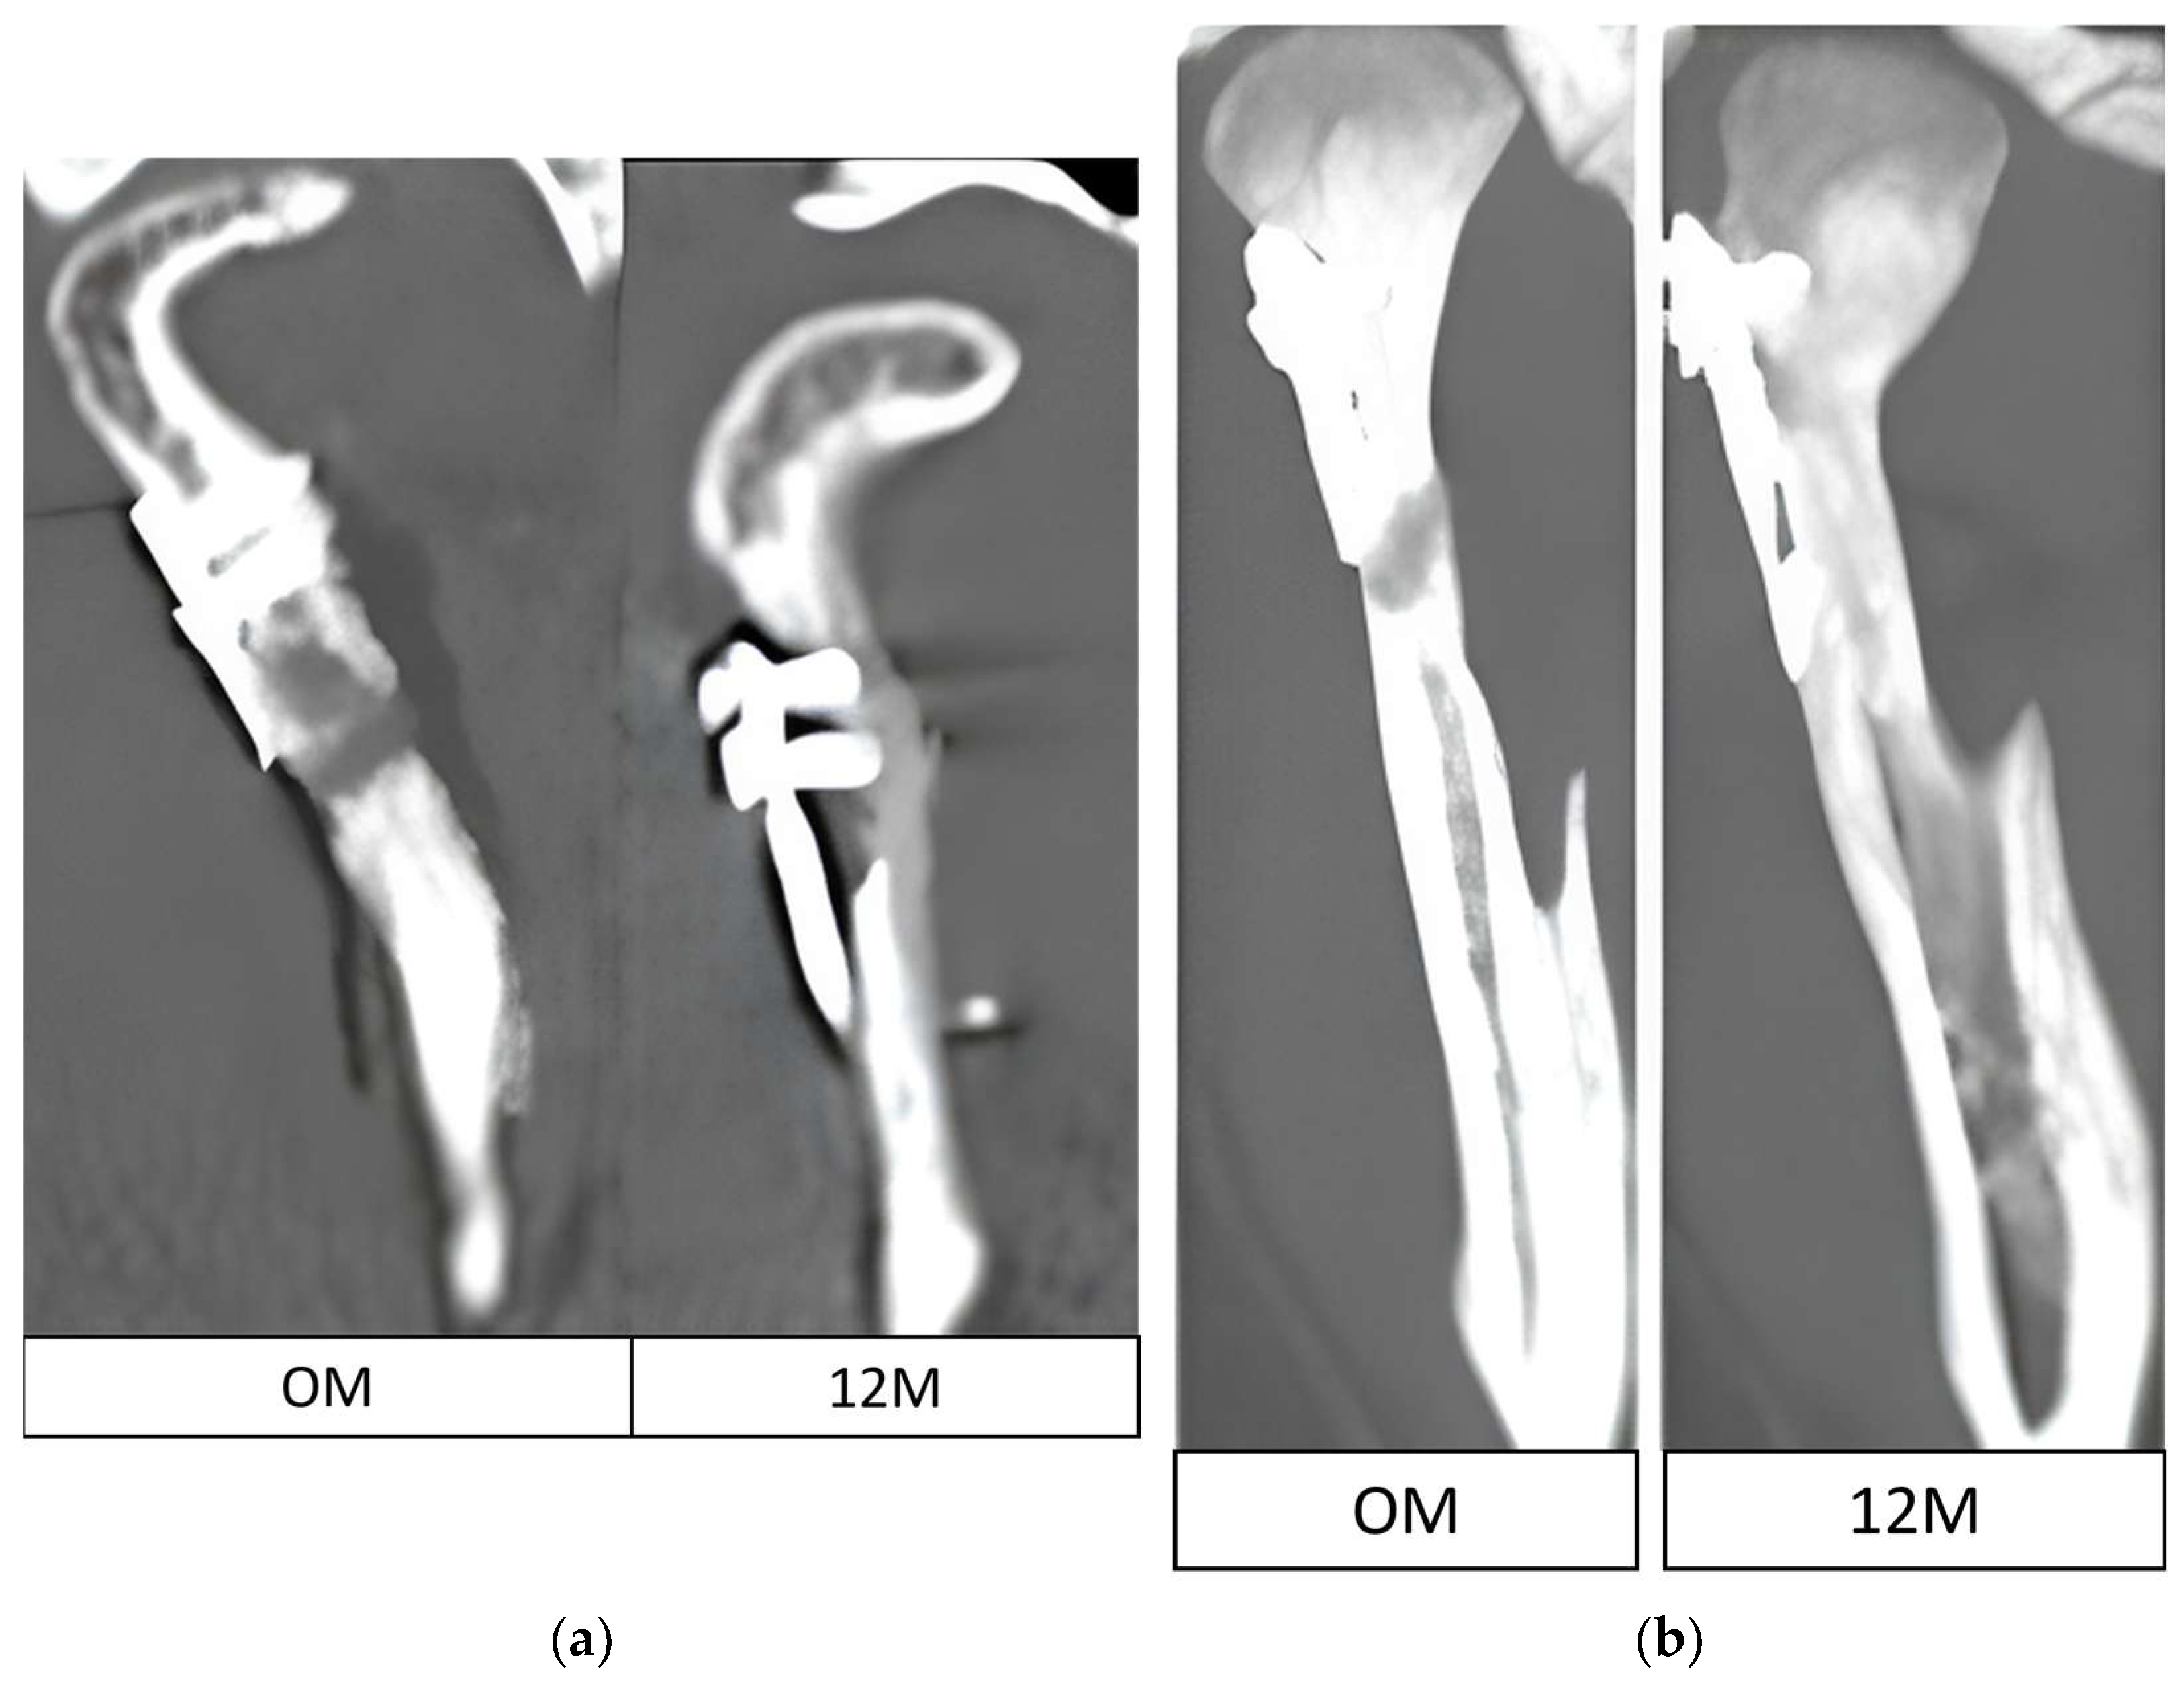

For each screw, the distance from the screw head to the bone border was measured parallel to the screw axis, immediately postoperatively and at 12-month follow-up. When resorption was observed around several screws, the mean value per plate was calculated. Measurements were taken in the frontal projection. A reference line perpendicular to the posterior border of the mandible was used to standardize orientation between scans.

The impact of the distance from the plate rim to the mandibular head lateral pole (in mm) is presented in

Figure 5. The values recorded ranged from those overlapping with the lateral pole (negative values) to a distance of as much as 20 mm. A statistical evaluation indicated that proximity to the lateral pole is a risk factor (

p < 0.05) for bone resorption at the plate rim (

Figure 5).

Osteosynthesis location was found to be related to resorption extent. Based on our findings, factors that induce resorption are not limited to plate insertion on the articular surface or covering the lateral pole of the mandibular head. Even lower osteosyntheses within the mandibular neck entail resorption. Only distant fixation, more than 14 mm away from the lateral pole, ensures no bone resorption at the osteosynthesis site. This finding is consistent with the biomechanical conclusions of Pavlychuk et al. [

Notably, the presented bone loss generally does not pose a threat to treatment outcomes, as it does not affect the loss mandibular ramus height. Exceptions here may include resorption observed at the upper rim of miniplates placed near the mandible head lateral pole. This may lead to involvement of the mandibular head in the resorptive process, shortening of the ramus and finally malocclusion. An exceptionally clinically devastating case may be seen in patients with significant bone resorption even on the lateral surface of the condylar process (away from the mandibular head), as this causes greater plate strain and may lead to plate fracture or pull-out of the fixation material due to exceeding the pull-out force for the residual screw fixation length (where the total length is usually only 6 mm). These results are in agreement with findings by Neff and Kolk [